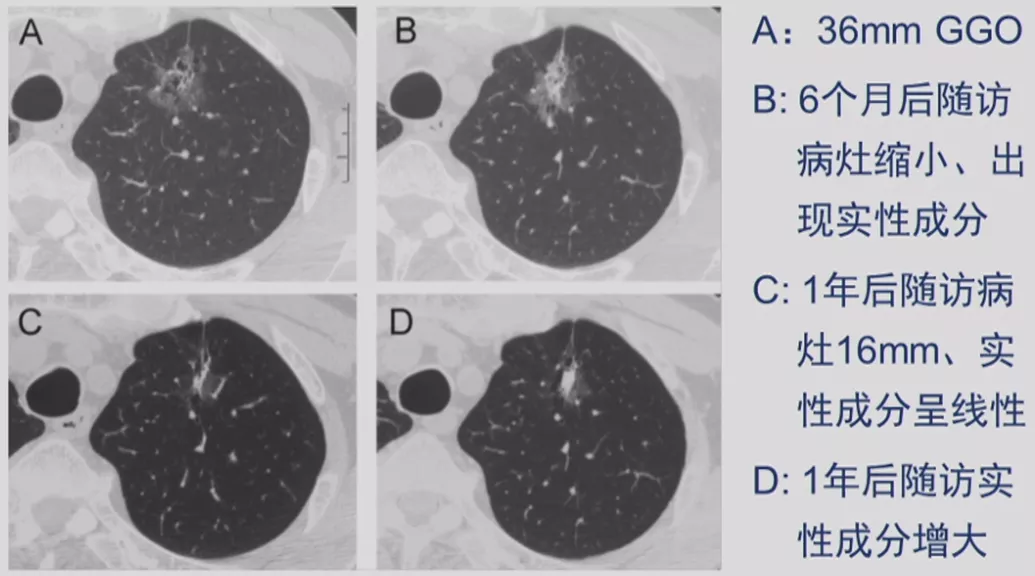

CT随访

1)病灶大小无变化、实性成分增多

这个结节大小没有太大变化,实性成分增多,这不是一个好征象,可以考虑手术。

2)病灶缩小、出现实性成分

容易被大家忽略的是结节的大小变小,但实性成分增多,值得大家重视。不要认为结节变小了就一定是良性。